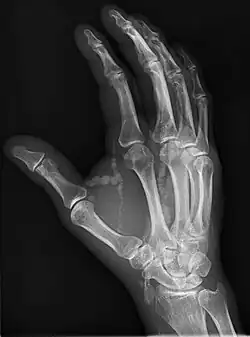

Hand radiograph showing tumoral calcinosis, PA radiograph of the right hand showing tumoral calcinosis-like metastatic calcification in a patient on dialysis. Dialysis alters calcium phosphate product (>70). Idiopathic tumoral calcinosis is autosomal dominant and is not associated with dialysis. Note the premature arterial calcification which is a clue that this is a renal patient. Vascular calcification contributes to an increase in morbidity. |

Tumoral calcinosis is a rare condition in which there is calcium deposition in the soft tissue in periarticular location, around joints, outside the joint capsule.[1] They are frequently (0.5–3%) seen in patients undergoing renal dialysis. Clinically also known as hyperphosphatemic familial tumoral calcinosis (HFTC), is often caused by genetic mutations in genes that regulate phosphate physiology in the body (leading to too much phosphate (hyperphosphatemia)). Best described genes that harbour mutations in humans are FGF-23,[2] Klotho (KL),[3] or GALNT3.[4] A zebrafish animal model with reduced GALNT3 expression also showed HFTC-like phenotype,[5] indicating an evolutionary conserved mechanism that is involved in developing tumoral calcinosis.

The name indicates calcinosis (calcium deposition) which resembles tumor (like a new growth). They are not true neoplasms – they don't have dividing cells. They are just deposition of inorganic calcium with serum exudate. Children and adolescents (6 to 25 years) are the most commonly affected. The symptom that the accumulations cause is not pain but swelling around joints. They have propensity to enlarge progressively and ulcerate the overlying skin and extrude. They are most common around shoulders, hips and elbows. Laboratory evaluation reveal normal serum calcium levels and hyperphosphatemia. Rarely ALP (alkaline phosphatase – an enzyme active at sites of bone formation) may be elevated. Treatment is normalization of serum phosphate levels and resection of lesions. Surgical removal should be complete and if part of it is left, recurrence is likely to occur. Cutting through the excised calcium deposition reveals semifluid calcium suspension in albumin encapsulated by fibrous tissue.